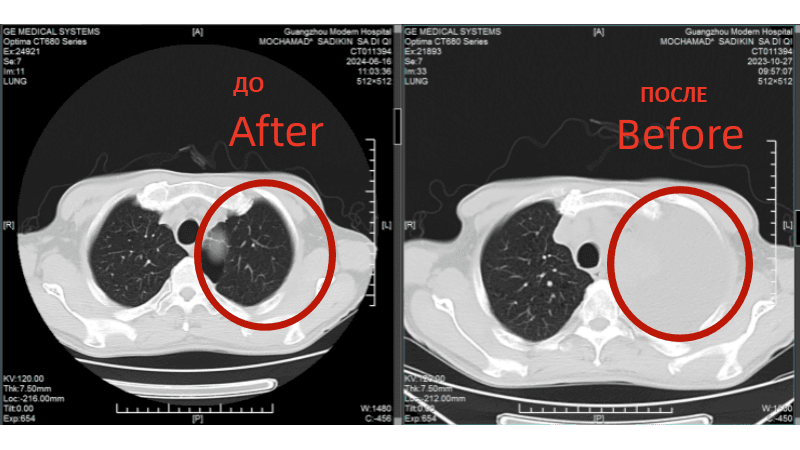

Сравнение КТ лёгких до и после лечения. Опухоль лёгких практически инактивирована

(Слева: до лечения, справа: после лечения)

Лечение дало ошеломляющие результаты: • После двух процедур КТ показало уменьшение очага в легком, а колоноскопия - значительное сокращение опухоли в кишечнике. • Исчезли мучительные симптомы: кашель и кровавый стул. • После семи сеансов опухоль в легком была практически полностью инактивирована, а в кишечнике - уменьшилась на 90%. Путь не был усыпан розами. Однажды у Радика резко упал уровень тромбоцитов, что грозило опасным кровотечением. В момент отчаяния именно настойчивость и профессионализм его лечащего врача, доктора Аденана, и всей команды спасли ситуацию. Быстро проведенная симптоматическая терапия стабилизировала состояние, и лечение было продолжено.